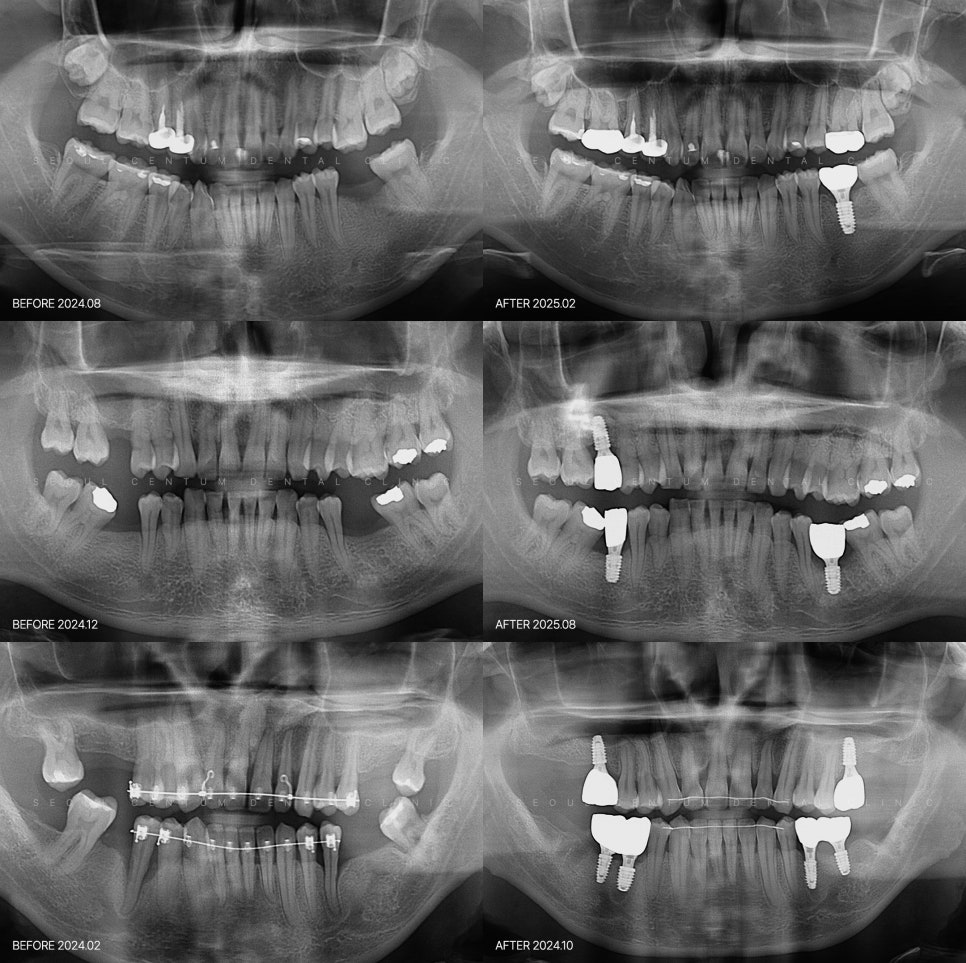

서울센텀치과의원 신사역의 네이버 블로그 원문을 보존한 아카이브 페이지입니다. 임플란트 카테고리의 임플란트하고 통증 기간 언제까지? 무조건 참는 게 답일까 글을 통해 병원의 한국어 정보 제공 방식과 진료 관련 안내 톤을 확인할 수 있습니다.

통증에 대한 막연한 걱정부터 줄여 나가야 합니다. 임플란트의 비용도 그렇지만 하고 나서 발생하는 통증이 심할 거라는 생각 때문에 받을지 말지 망설이는 분들도 계시더라고요. 여기에 민감하게 반응하는 것도 사실이죠. 당분간 생활할 때 불편감이 지속되니까요. 체계적인 절차에 따라 진행되는 치료라서 관리 가능한 내에서 발생하...